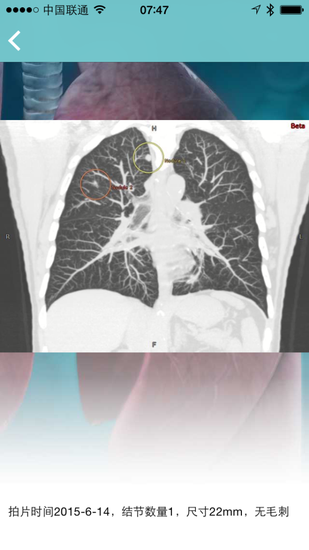

“肺结节伴侣”app截图

值得关注的是,一款名为“肺结节伴侣”的苹果手机app成为论坛一大亮点。该手机app系世界范围内首个应用ResearchKit软件架构管理肺结节患者的医学app,它为医生持续随访肺结节患者提供了非常方便的工具。患者通过定期填写问卷,可以实时了解自己的肺癌风险程度;医生可以远程随访患者,并服务患者和进行医学研究。患者利用该app可轻松获得整合数据资料,为自己选择最优的治疗方式,做到通过手机app掌上防治肺癌。据介绍,目前全国已有40余家三甲医院预备全面推广这款手机软件,芜湖uhealth卫健康公司将为其提供IT技术支持。